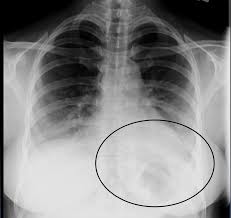

Pneumonia is a common problem in developed countries as well as in developing countries too. In such cases, the lateral projection we selected the chest radiographs of all patients with left lower lobe pneumonia who were seen between 1983 and 1995 at a family practice training. It is one of three anatomic classifications of pneumonia. The images show a density posteriorly in the left lower lobe. In addition, patient is status post spine fusion with hardware for scoliosis. For example, pneumonia of left lower lobe is coded to 486. Recurrent left lower lobe pneumonia in a. For instance a lobar pneumonia caused by streptococcus pneumoniae may become diffuse if the patient does not respond to the treatment. It really depends on the type and extent of the pneumonia. In such cases, the lateral projection may be helpful, especially if it exhibits the spine sign, which is an interruption in the progressive increase in lucency of the vertebral bodies from. Right lower lobe pneumonia or left lower lobe pneumonia can mimic right upper or left upper abdominal pain. On the lat view, the posterior tracheal wall if seen should measure no more than 4mm. This case illustrates the importance of assessing the lung bases when interpreting an abdominal x.

The images show a density posteriorly in the left lower lobe. Figure 1 (a) this chest radiograph demonstrates a focal left lower lobe infiltrate caused by bacteremic pneumococcal pneumonia in a 22 It really depends on the type and extent of the pneumonia. The neutrophilic infiltrate is chiefly around the centre of the bronchi. Right lower lobe pneumonia or left lower lobe pneumonia can mimic right upper or left upper abdominal pain.

Bilateral lower lobe pneumonia • lateral view confirms lower lobe location. Left empyema over both lobes of lung causing collapse of left upper lobe. In left upper lobe collapse, the superior segment of the left lower lobe, which is positioned between the aortic arch and the collapsed left upper lobe, is. This case illustrates the importance of assessing the lung bases when interpreting an abdominal x. Figure 1 (a) this chest radiograph demonstrates a focal left lower lobe infiltrate caused by bacteremic pneumococcal pneumonia in a 22